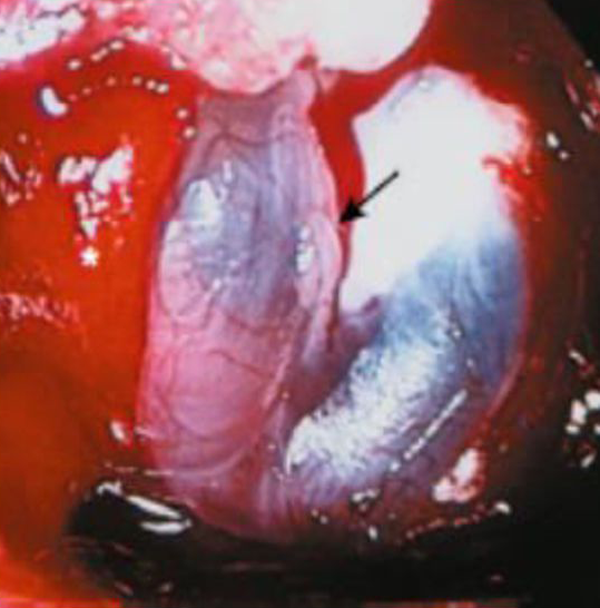

De acuerdo con la clasificación de Espósito–Dusik (Tabla 2),5 el nivel de reparación debe ser llevado a cabo acorde al grado de fístula producida,5 siendo Grado 0: donde no hay una fístula presente y no es necesaria la reparación; algunos autores recomiendan la aplicación monocapa de Duragen® a nivel intraselar extradural, reduciendo el espacio muerto intraselar y promoviendo la hemostasia; Grado 1: reportado en muchos centros como el grado de fístula más frecuente; suele aparecer como un babeo espontáneo o bien luego de la aplicación de una maniobra de Valsalva, sin un defecto diafragmático evidente (ver Figura 1). Para esto, puede utilizarse un material sintético de barrera más un sellador dural que actúe de contenedor, evitando el uso de incisiones adicionales para obtener materiales autólogos. A pesar de esto, en casos de macroadenomas que dejan un espacio intraselar considerable luego de su remoción, es factible colocar grasa y colgajo mucoperióstico de turbina media o septum nasal, como contenedores, con misma eficacia, pero con incisiones adicionales; Grado 2: en este caso, se produce una fístula moderada que lleva líquido al espacio intraselar, con un defecto diafragmático evidente. La reparación multicapa con material autólogo es requerida: grasa, fascia lata y mucoperióstio. Una combinación muy efectiva es la colocación de grasa intraselar como sellador, más Duragen® intraselar-extradural, o bien cualquier otro aloinjerto que actúe de contenedor; Grado 3: grado donde se produce una fístula de alto flujo con un defecto diafragmático dural amplio, consecuencia de una apertura deliberada del diafragma selar, produciéndose con mayor frecuencia en abordajes transesfenoidales extendidos. Requerirá de una reparación multicapa que abarque el espacio intraselar y el seno esfenoidal, utilizando una combinación de materiales autólogos y sintéticos, que actúen de selladores y contenedores. También, es factible la utilización de un drenaje espinal transitorio por 48 horas.

Figura 1. Imagen intraquirúrgica de una fístula grado 1.